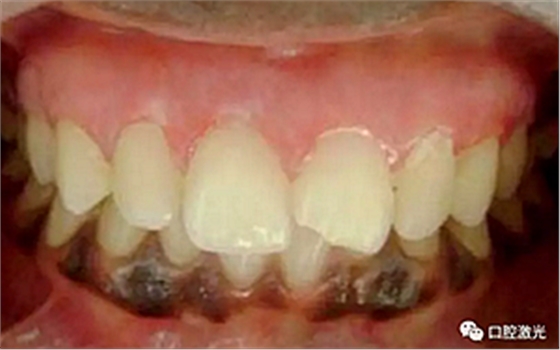

患者22岁,女性,主诉牙龈发黑。口腔检查显示牙龈部位呈黑色,但软组织健康,没有表皮粗糙或水肿现象。计划使用半导体激光进行治疗。手术前患者无需表麻或局麻。采用光纤接触方式,激光功率设定为1.5W至2W,连续模式。气化黑色牙龈区域上皮组织。不断重复该过程,直至足够深度的牙龈软组织表皮被去除干净。患者术后需采用漱口水进行口腔护理。

术前